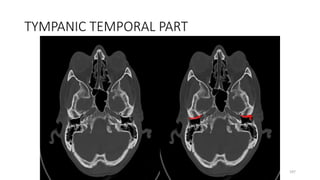

TYMPANIC TEMPORAL PART

197

TYMPANOSQUAMOUS FISSURE